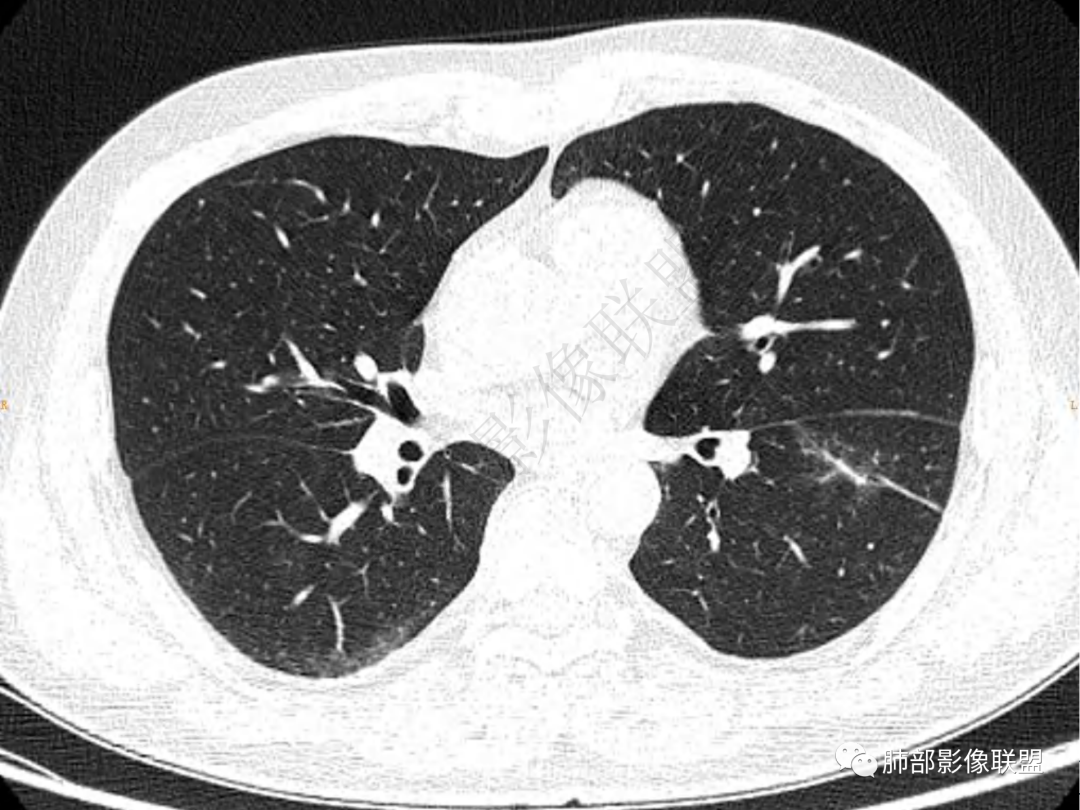

1.中年男性,咳嗽咳痰20余天,间断咯血2周

2.左肺下叶团片影,跨背段及内前基底段,实性部分类椭圆形,密度不甚均匀,可见毛刺及棘状突起,未见典型分叶及胸膜凹陷。病灶上下缘可见相应肺段支气管旁进侧出,管壁轻度增厚,未见狭窄阻塞。

3.周边较大范围磨玻璃影,边界相当模糊,小叶增厚明显。注意叶裂另一侧、左肺舌段亦可见磨玻璃影及增厚的小叶间隔。未见明确卫星病灶。

4.实性部分不均匀环形强化并显示一小范围低密度坏死区或空洞。较之肺窗,整体纵隔窗范围较小,提示病灶并不十分密实。抑或为不同时段图像。

5.双肺门及纵隔未见增大淋巴结。未见胸腔积液。